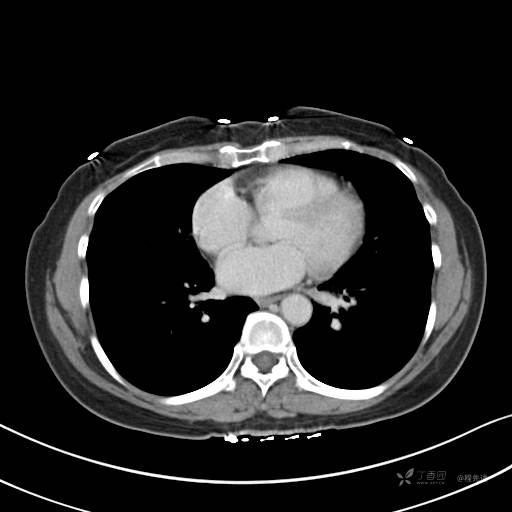

增强动脉期

动脉期CT值约74HU